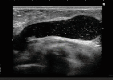

エコー症例

豊胸ヒアルロン酸注入で起こるトラブル

逆に大き過ぎる塊で入れると、分解できずに残ってしまい、硬いしこりになるトラブルに発展。

THE CLINICではそんな問題を完治すべく、最先端のエコーを導入して治療にあたっています。

分解できなかった部分はしこりとして残存